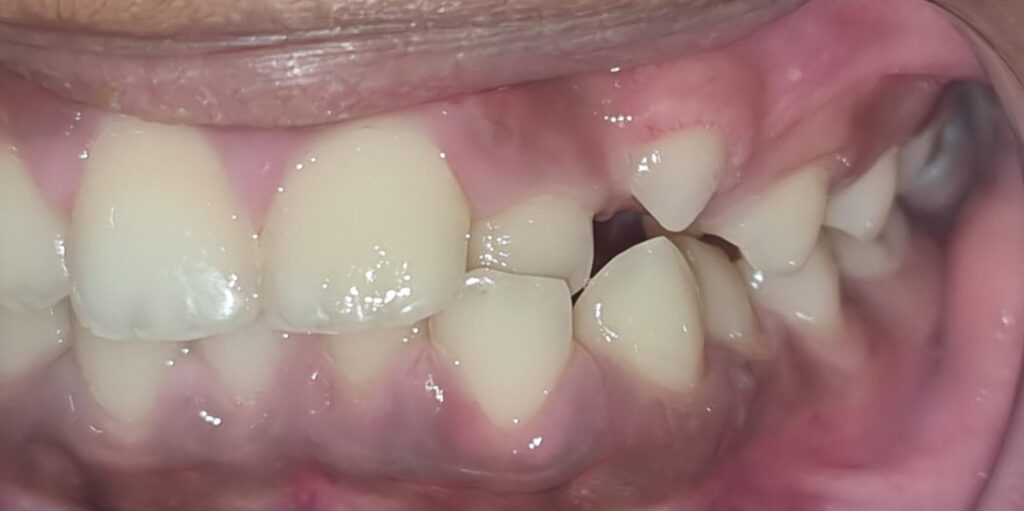

56) Ayaan Manaswala – extreme severe crowding and highly placed canines.